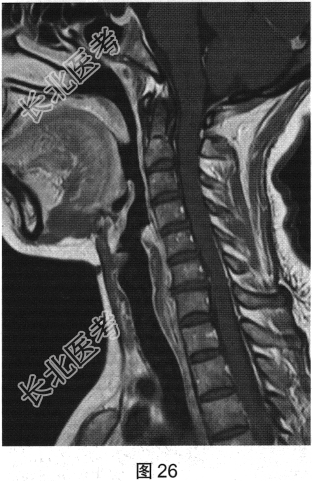

- 多项选择题2.[提示]患者行脊柱MRI平扫及增强检查,如图25、图26所示。关于MRI检查结果, 描述正确的是( )

A、脊髓未见异常

B、颈髓T2WI可见多发片状高信号影

C、脊髓空洞

D、部分胸髓T2WI可见多发片状高信号影

E、脊髓肿胀

F、MRI增强检查可见小片状强化

- 多项选择题3.根据脊髓和颅脑MRI表现,病变应诊断为( )

D、多发性硬化